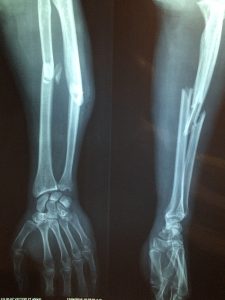

That's when he pushed my father underwater. My father got away and swam back up. He just said, "Don't make me hit you," and the jet skiier calmed down a little. Until he saw the tangle of metal that was once his jet ski, that is... The jet skiier (who we found out later had shattered his collar bone and most of the bones in right arm AND leg) started trying to swim toward the jet ski. My father tried to hold him back but didn't want to hurt him - the jet skier managed to get back to the jet ski and STARTED TO TRY TO TURN IT BACK ON.